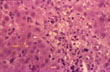

Kupffer cell hyperplasia

Fig 54 - KUPFFER CELL HYPERPLASIA: With cells full of lipofuscin an bile, result of phagocytosis of disrupted hepatocytes. Nodules of these cells may persist after healing (late nodules of Spatknoetchen).